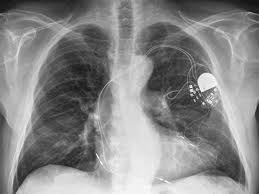

심장마비의 위험이 큰 환자들의 경우 삽입형 제세동기를 삽입한다. 삽입형 제세동기는 위험한 부정맥을 전기충격으로 소멸시키는 기계적 장치라고 한다.

환자에서 심실빈맥이나 심실세동과 같은 위험한 부정맥이 발생하면, 이를 스스로 감지해 전기충격을 가함으로써 환자의 생명을 구할 수 있다고 한다.